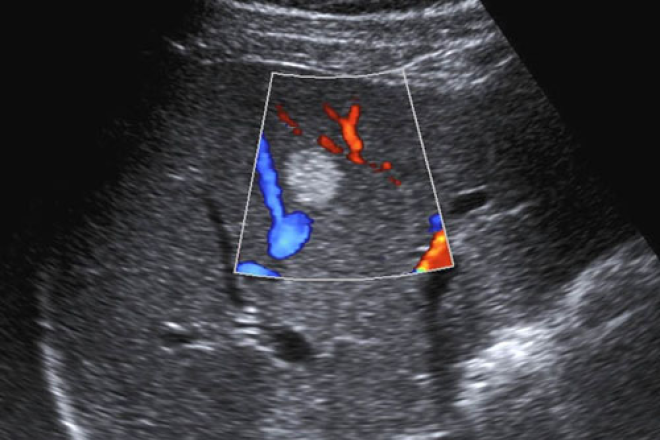

Los hallazgos típicos son patrón en mosaico, formación septal, sonolucencia periférica (halo), sombra lateral producida por una pseudocápsula fibrosa, reforzamiento posterior, hipervasculridad arterial, nódulos perinodulares hijos.

Se ha descrito un patrón en canasta en el Doppler. Los hallazgos típicos del HCC en el Doppler con color son señales de forma de onda pulsátiles aferentes.